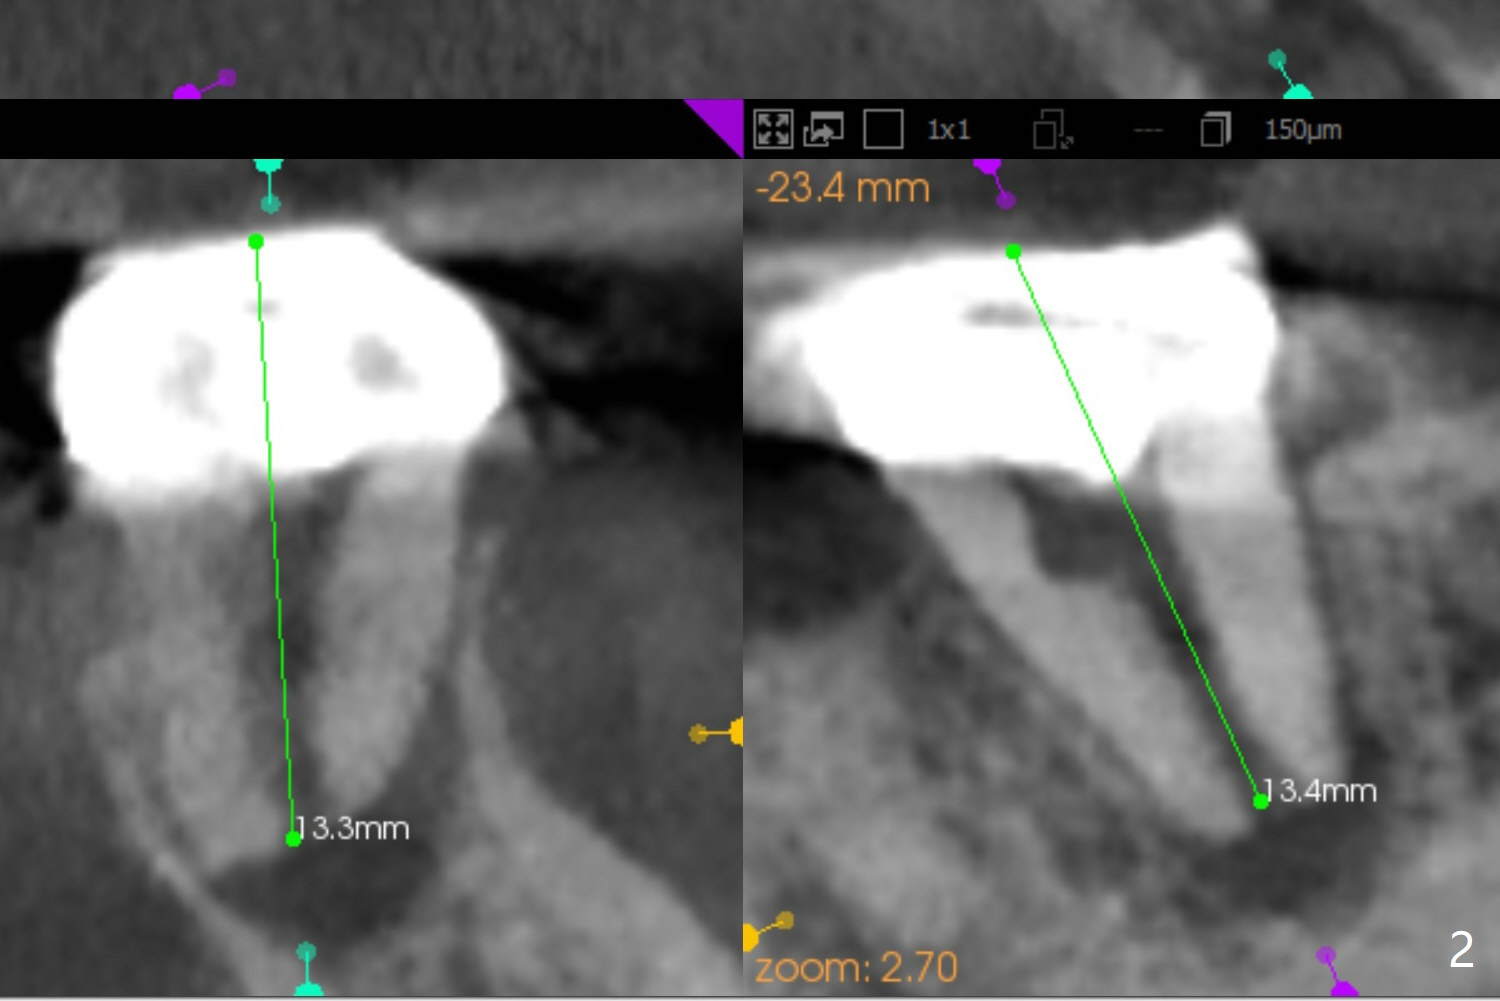

A 54-year-old woman will return for #18 extraction and implant 1 or 2 years post implants at #19 and #30. In fact the tooth has had incomplete RCT with PARL. Reanalysis of CT taken on 02/02/2017 (before RCT) shows that RCT retreatment should not be too difficult (Fig.1,2). If the treatment turns out to be not successful, a 5x10 mm immediate implant will be done with a possible 25 degree angled abutment (Fig.3,4).